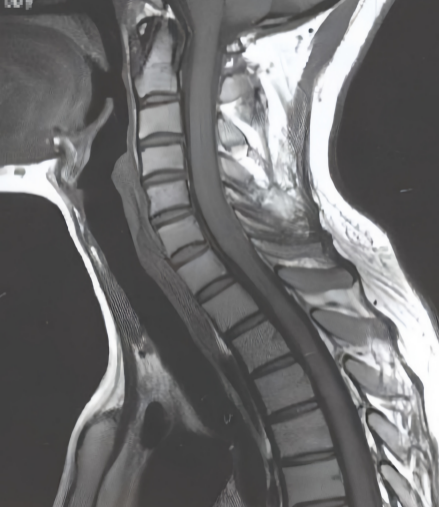

3.MRI(磁共振)检查。MRI是目前诊断最可靠的检查方法,对于有颈椎外伤史且有神经损伤表现的成人患者应尽早行MRI检查。MRI检查可以很清楚地看出颈椎管腔狭窄、颈部脊髓明显受压后会是什么样的表现。在伤后早期,就可明确脊髓损伤、脊髓受压部位、椎管内变化等表现;脊髓损伤晚期,可判断脊髓信号改变等。

▲正常椎管腔通畅

▲异常椎管腔变窄